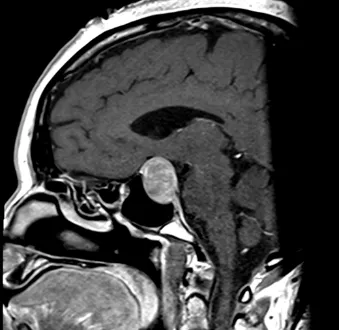

Pre- and Post-Op Pituitary Macroadenoma

Pre-Op Pituitary Tumor Image 2

Pre-Op Image of Pituitary Tumor